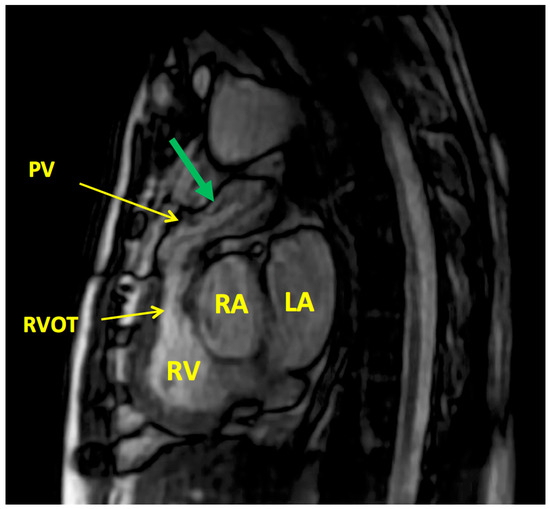

6.3. Post-Operative and Long-Term Follow-Up Imaging